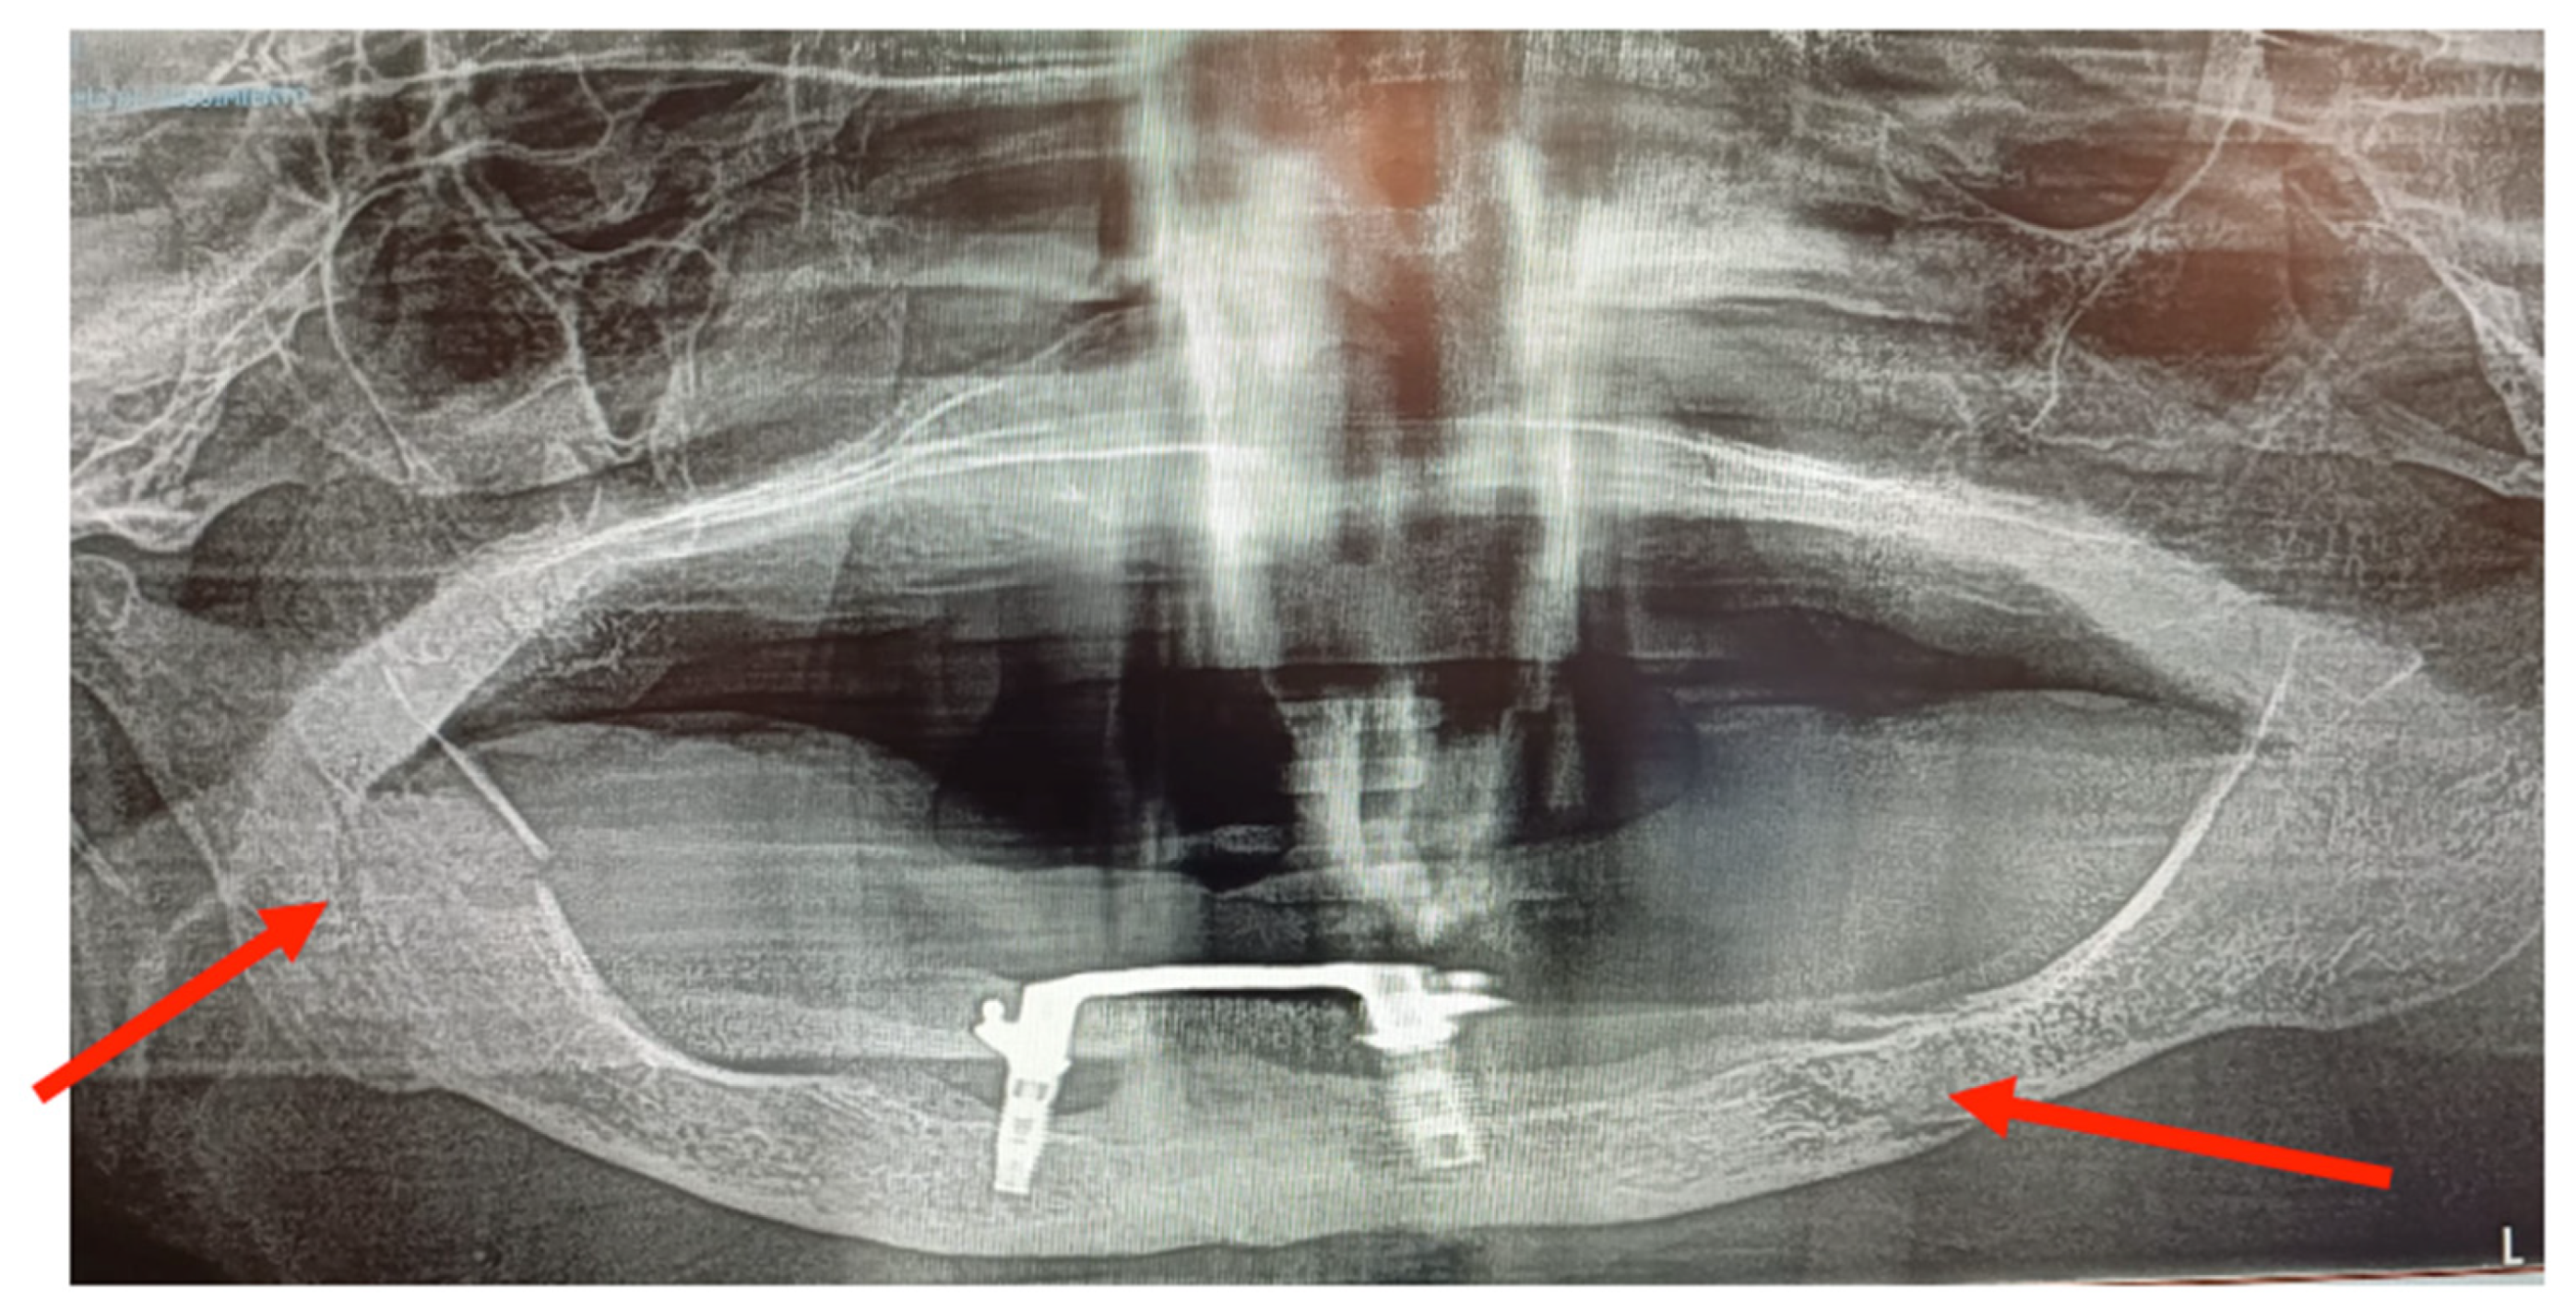

3.1. Case 1

3.2. Case 2

| Location | Left parasymphyseal | 2 (33.3%) |

| Left body | 3 (50%) | |

| Bifocal (left body and right ramus) | 1 (16.67%) | |

| Fracture pattern | Simple | 5 (83.3%) |

| Bifocal | 1 (16.67%) | |

| Etiology | Peri-implantitis | 3 (50%) |

| Traumatism | 1 (16.67%) | |

| Osteonecrosis | 2 (33.3%) | |